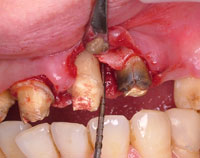

天然歯の歯周組織の骨を回復させ、隣在歯にインプラントを埋入した症例

写真にある変色歯は、歯根破折及び虫歯で歯質が感染崩壊しており、 歯周外科にて確定診断を行い、抜歯しております。

術前 エムドゲイン適応 術後